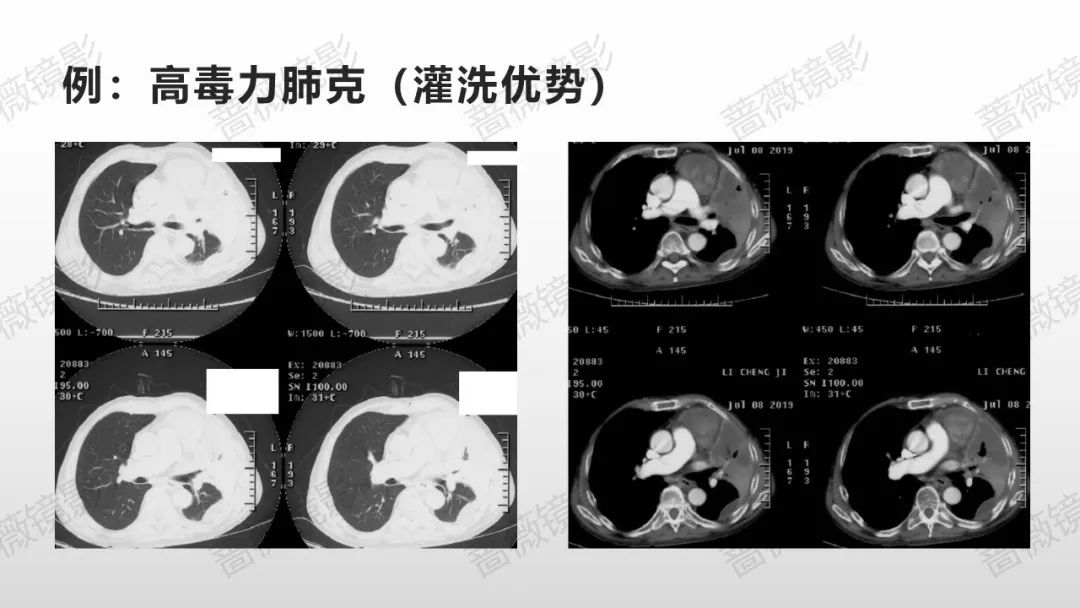

我对支气管肺泡灌洗液mNGS病原学检出的深层思考

虚拟导航引导超细内镜精准加压BAL能够解决什么问题?其短板如何弥补?